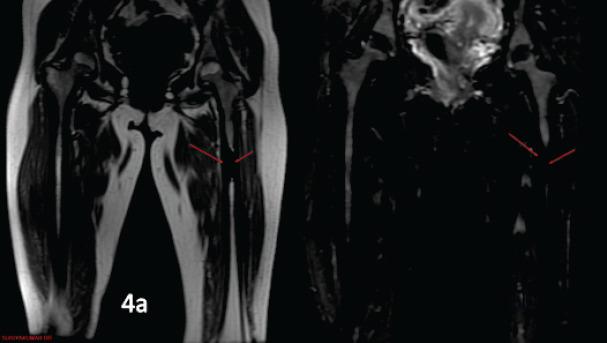

Melorheostosis is a rare condition affecting the bones and has only been occasionally reported. We herein report a case of melorheostosis affecting left femur and tibia which was diagnosed based on clinical and radiological features and managed with bisphosphonates.

A 28-year-old female patient presented with complaints of pain over left knee and thigh for the past 3 months. To evaluate the cause of pain X-ray and magnetic resonance imaging were done, which revealed characteristic candle dripping wax appearance suggestive of melorheostosis. After arriving at the diagnosis patient was started on nonsteroidal anti-inflammatory drugs and pamidronate which provided symptomatic betterment patient has now been followed up for past 1 year and is symptom free.

骨蜡油样骨病是一种影响骨骼的罕见病症,仅有零星报道。我们在此报告一例累及左股骨和胫骨的骨蜡油样骨病病例,该病例根据临床和放射学特征得以诊断,并采用双膦酸盐进行治疗。

一名28岁女性患者,过去3个月来一直诉说左膝和大腿疼痛。为评估疼痛原因,进行了X线和磁共振成像检查,结果显示出具有特征性的烛泪样外观,提示为骨蜡油样骨病。确诊后,患者开始服用非甾体类抗炎药和帕米膦酸盐,症状有所改善。患者现已接受了1年的随访,目前无症状。